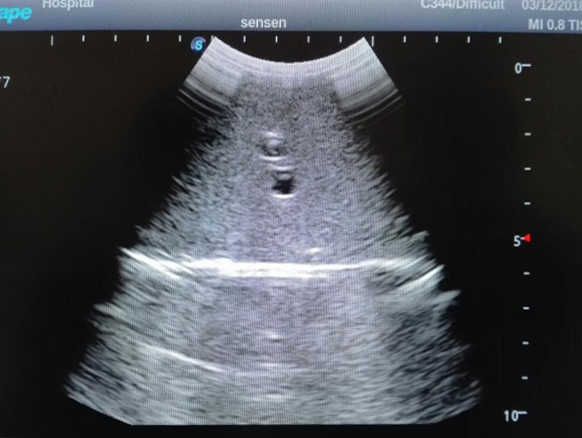

1)  Ideal for trainings like ultrasound-guided abdominocentesis with visible ascites flowing out, ultrasound-guided femoral artery & venous puncture

2)  High quality ultrasound image with clear structures like gallbladder, liver, intestines, arteries and veins etc.